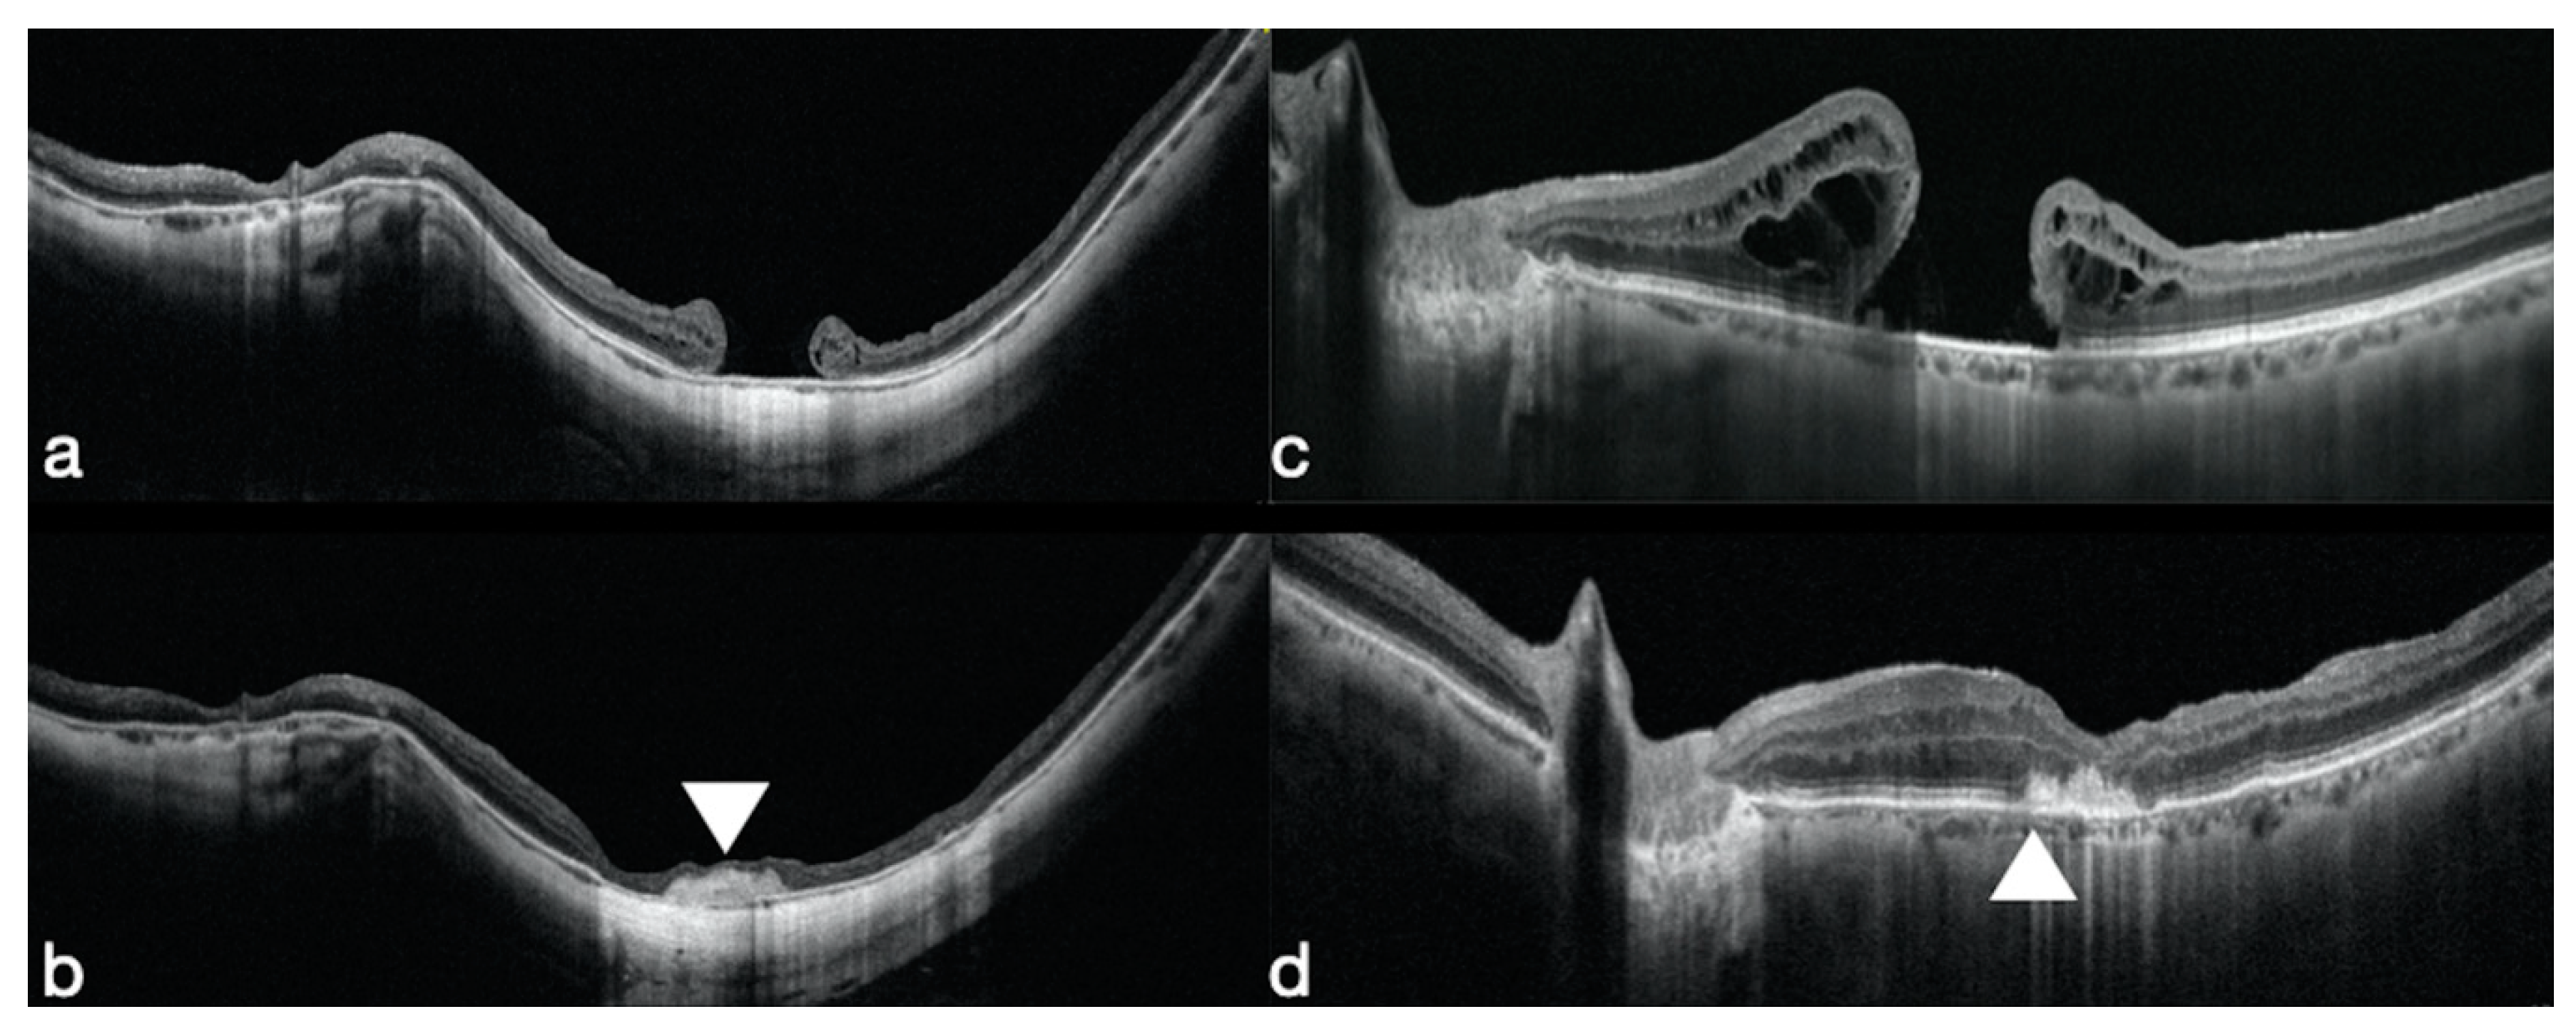

3.1. Macular Holes that Failed to Close

- Rizzo, S.; Caporossi, T.; Tartaro, R.; Finocchio, L.; Franco, F.; Barca, F.; Giansanti, F. A Human Amniotic Membrane Plug to Promote Retinal Breaks Repair and Recurrent Macular Hole Closure. Retina 2019, 39 (Suppl. 1), S95–S103. [Google Scholar] [CrossRef]

- Imai, M.; Iijima, H.; Gotoh, T.; Tsukahara, S. Optical coherence tomography of successfully repaired idiopathic macular holes. Am. J. Ophthalmol. 1999, 128, 621–627. [Google Scholar] [CrossRef]

- Kang, S.W.; Ahn, K.; Ham, D.I. Types of macular hole closure and their clinical implications. Br. J. Ophthalmol. 2003, 87, 1015–1019. [Google Scholar] [CrossRef]